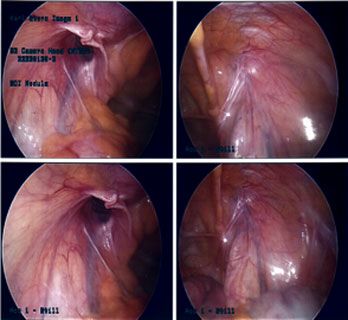

Good size recurrent inguinal hernia